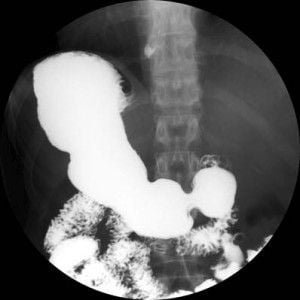

Noticias y Articulos Tránsito esofagogastroduodenal (E.G.D.) – Parte II 21 junio, 2012 Tidito Imágenes Transito Esofagogastroduodenal (E.G.D.) Seriadas Bulbares Duodeno en Anteroposterior